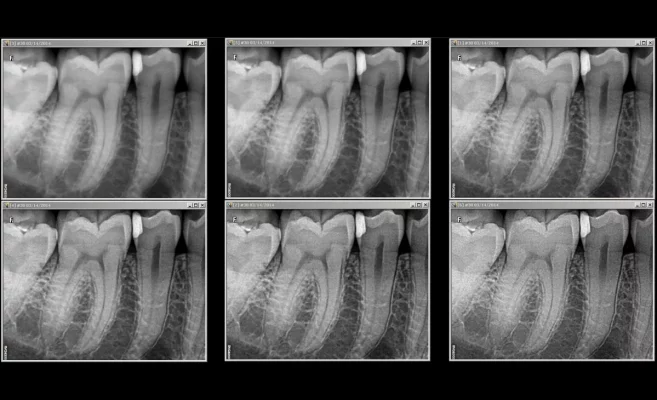

- Reálné rozlišení 24 lp/mm poskytuje detailní informace pro přesnou diagnózu

Kvalita snímku podle Vašich představ

S RVG 6200 je ideální snímek na dosah pouze několik kliknutí myší. Tři anatomické režimy

zvýraznění – endo, perio, dentin-sklovina spolu s dynamickým posuvníkem filtru ostrosti umožňují

sledovat v reálném čase kontrast a jas upravovaného snímku. Snímek můžete doladit šesti úrovněmi ostrosti tak, aby přesně odpovídal Vašim požadavkům. Vaši práci může dále urychlit volba a uložení kombinace anatomického režimu a úrovně filtru ostrosti jako výchozího nastavení.